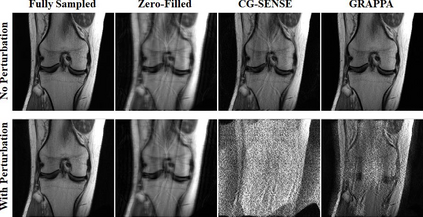

Although deep learning (DL) has received much attention in accelerated MRI, recent studies suggest small perturbations may lead to instabilities in DL-based reconstructions, leading to concern for their clinical application. However, these works focus on single-coil acquisitions, which is not practical. We investigate instabilities caused by small adversarial attacks for multi-coil acquisitions. Our results suggest that, parallel imaging and multi-coil CS exhibit considerable instabilities against small adversarial perturbations.